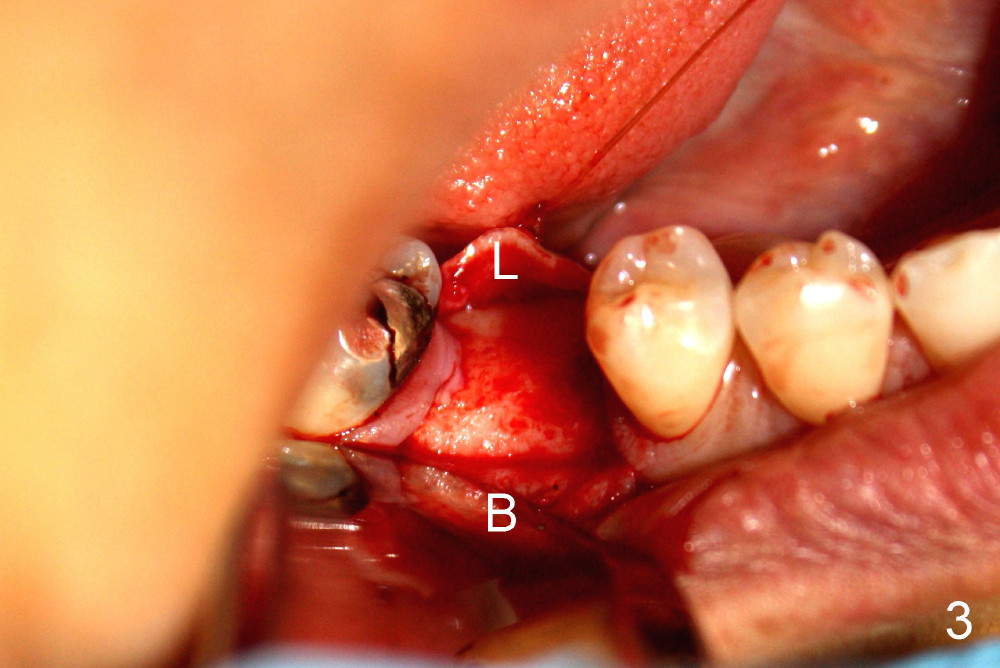

切口翻瓣(颊(B)舌(L)侧)后,证实骨头宽度(图三)。为了掌握好深度,术前术中多拍摄X光片几次,并且进行测量,反复问自己看清楚神经没有(与否):神经管上缘在那里?如果没有把握,宁可用短一些植牙,给自己多一些余地。其实植牙长度不重要,而直径更重要。